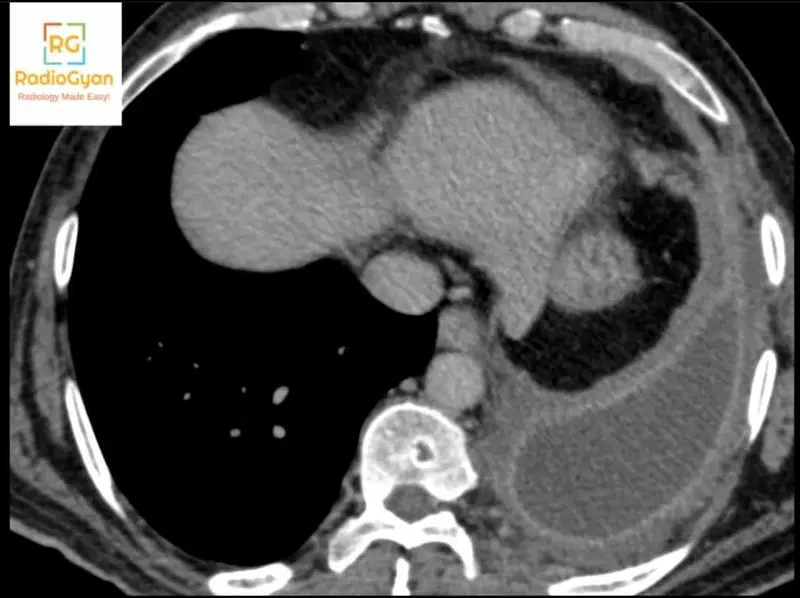

The Split Pleura Sign represents separation and thickening of both the visceral pleura and parietal pleura layers by an accumulation of pleural fluid, most commonly indicating pleural empyema. This sign develops when infected pleural fluid accumulates between the two pleural layers, causing them to become individually visible and separated on imaging.

The sign is named for its appearance of the pleural membrane appearing as two distinct split layers rather than a single continuous structure. The descriptive term reflects the visual separation of the visceral pleura (innermost layer) from the parietal pleura (outer layer) by the intervening pleural effusion, creating a characteristic split appearance on cross-sectional imaging.

In pleural empyema, bacterial or fungal infection triggers an inflammatory response within the pleural space. This inflammatory process causes both the visceral pleura and parietal pleura layers to become edematous and hyperenhanced on contrast-enhanced CT. As purulent fluid accumulates and exerts pressure between these two thickened pleural layers, they are mechanically separated and pushed apart. The combination of pleural thickening with fluid separation makes both layers individually conspicuous on imaging, whereas in simple pleural effusion without infection, pleural thickening is typically absent or minimal. The pleural fluid volume typically exceeds 30 mm in thickness when the Split Pleura Sign is present.